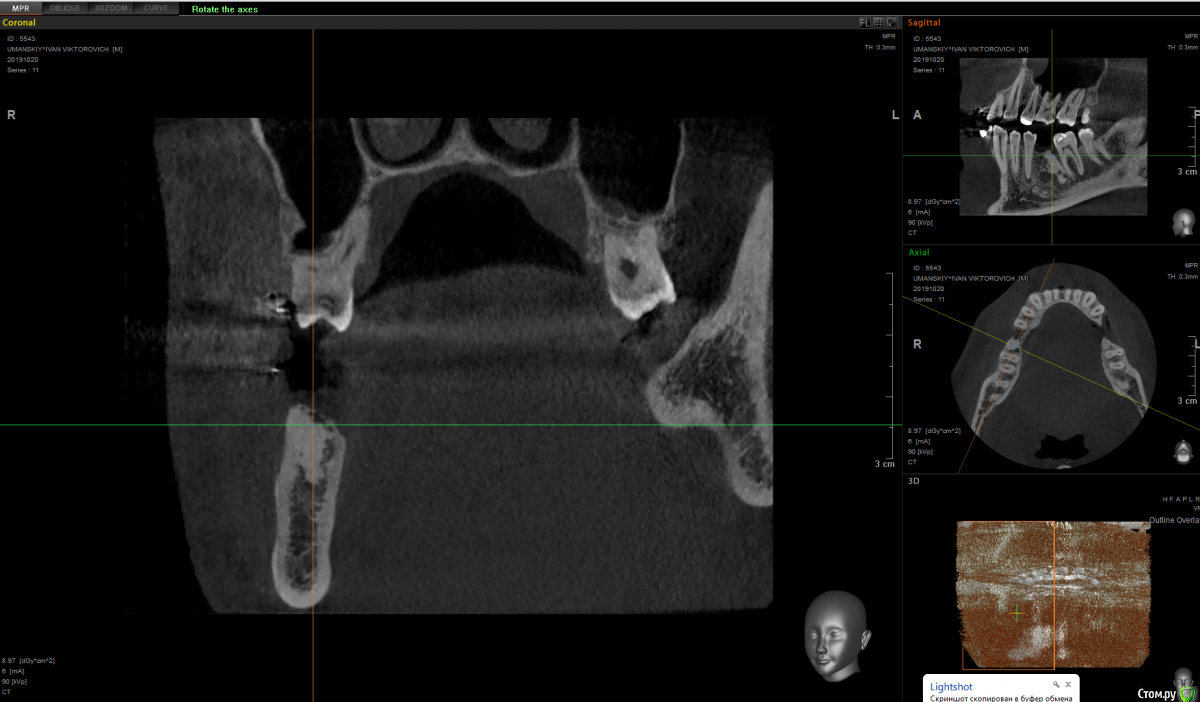

It'sGeorgy Опубликовано 15 января, 2020 Поделиться Опубликовано 15 января, 2020 Здравствуйте!На 2ом прикреплении явно следствие, на 3 и 4 - причина. Вижу 2 варианта развития событий:1: Разрезать, отслоиться. Посмотреть что явилось причиной, удалить причину. Начать готовить ложе под имплантат. 4.0 фрезой провалиться в полость кисты, попытаться извлечь ее через ложе. Поставить имплантат.2: Если через ложе извлечь не удастся, то пойти вестибулярным доступом. Извлечь. Графт, мембрана. 5 мес отдыха. Имплантат. Кто подобным уже занимался, подскажите, насколько перспективен первый вариант? Возможно ли по КТ понять что явилось причиной? На корень не особо похоже. Для остеомы тоже нетипичная картина. Ссылка на комментарий

shy Опубликовано 15 января, 2020 Поделиться Опубликовано 15 января, 2020 (изменено) резидуальная пошел бы через вестибулярный доступ , с графтом или без на усмотрение оперирующего . P.S причину уже удалили до Вас Изменено 15 января, 2020 пользователем shy 1 Ссылка на комментарий